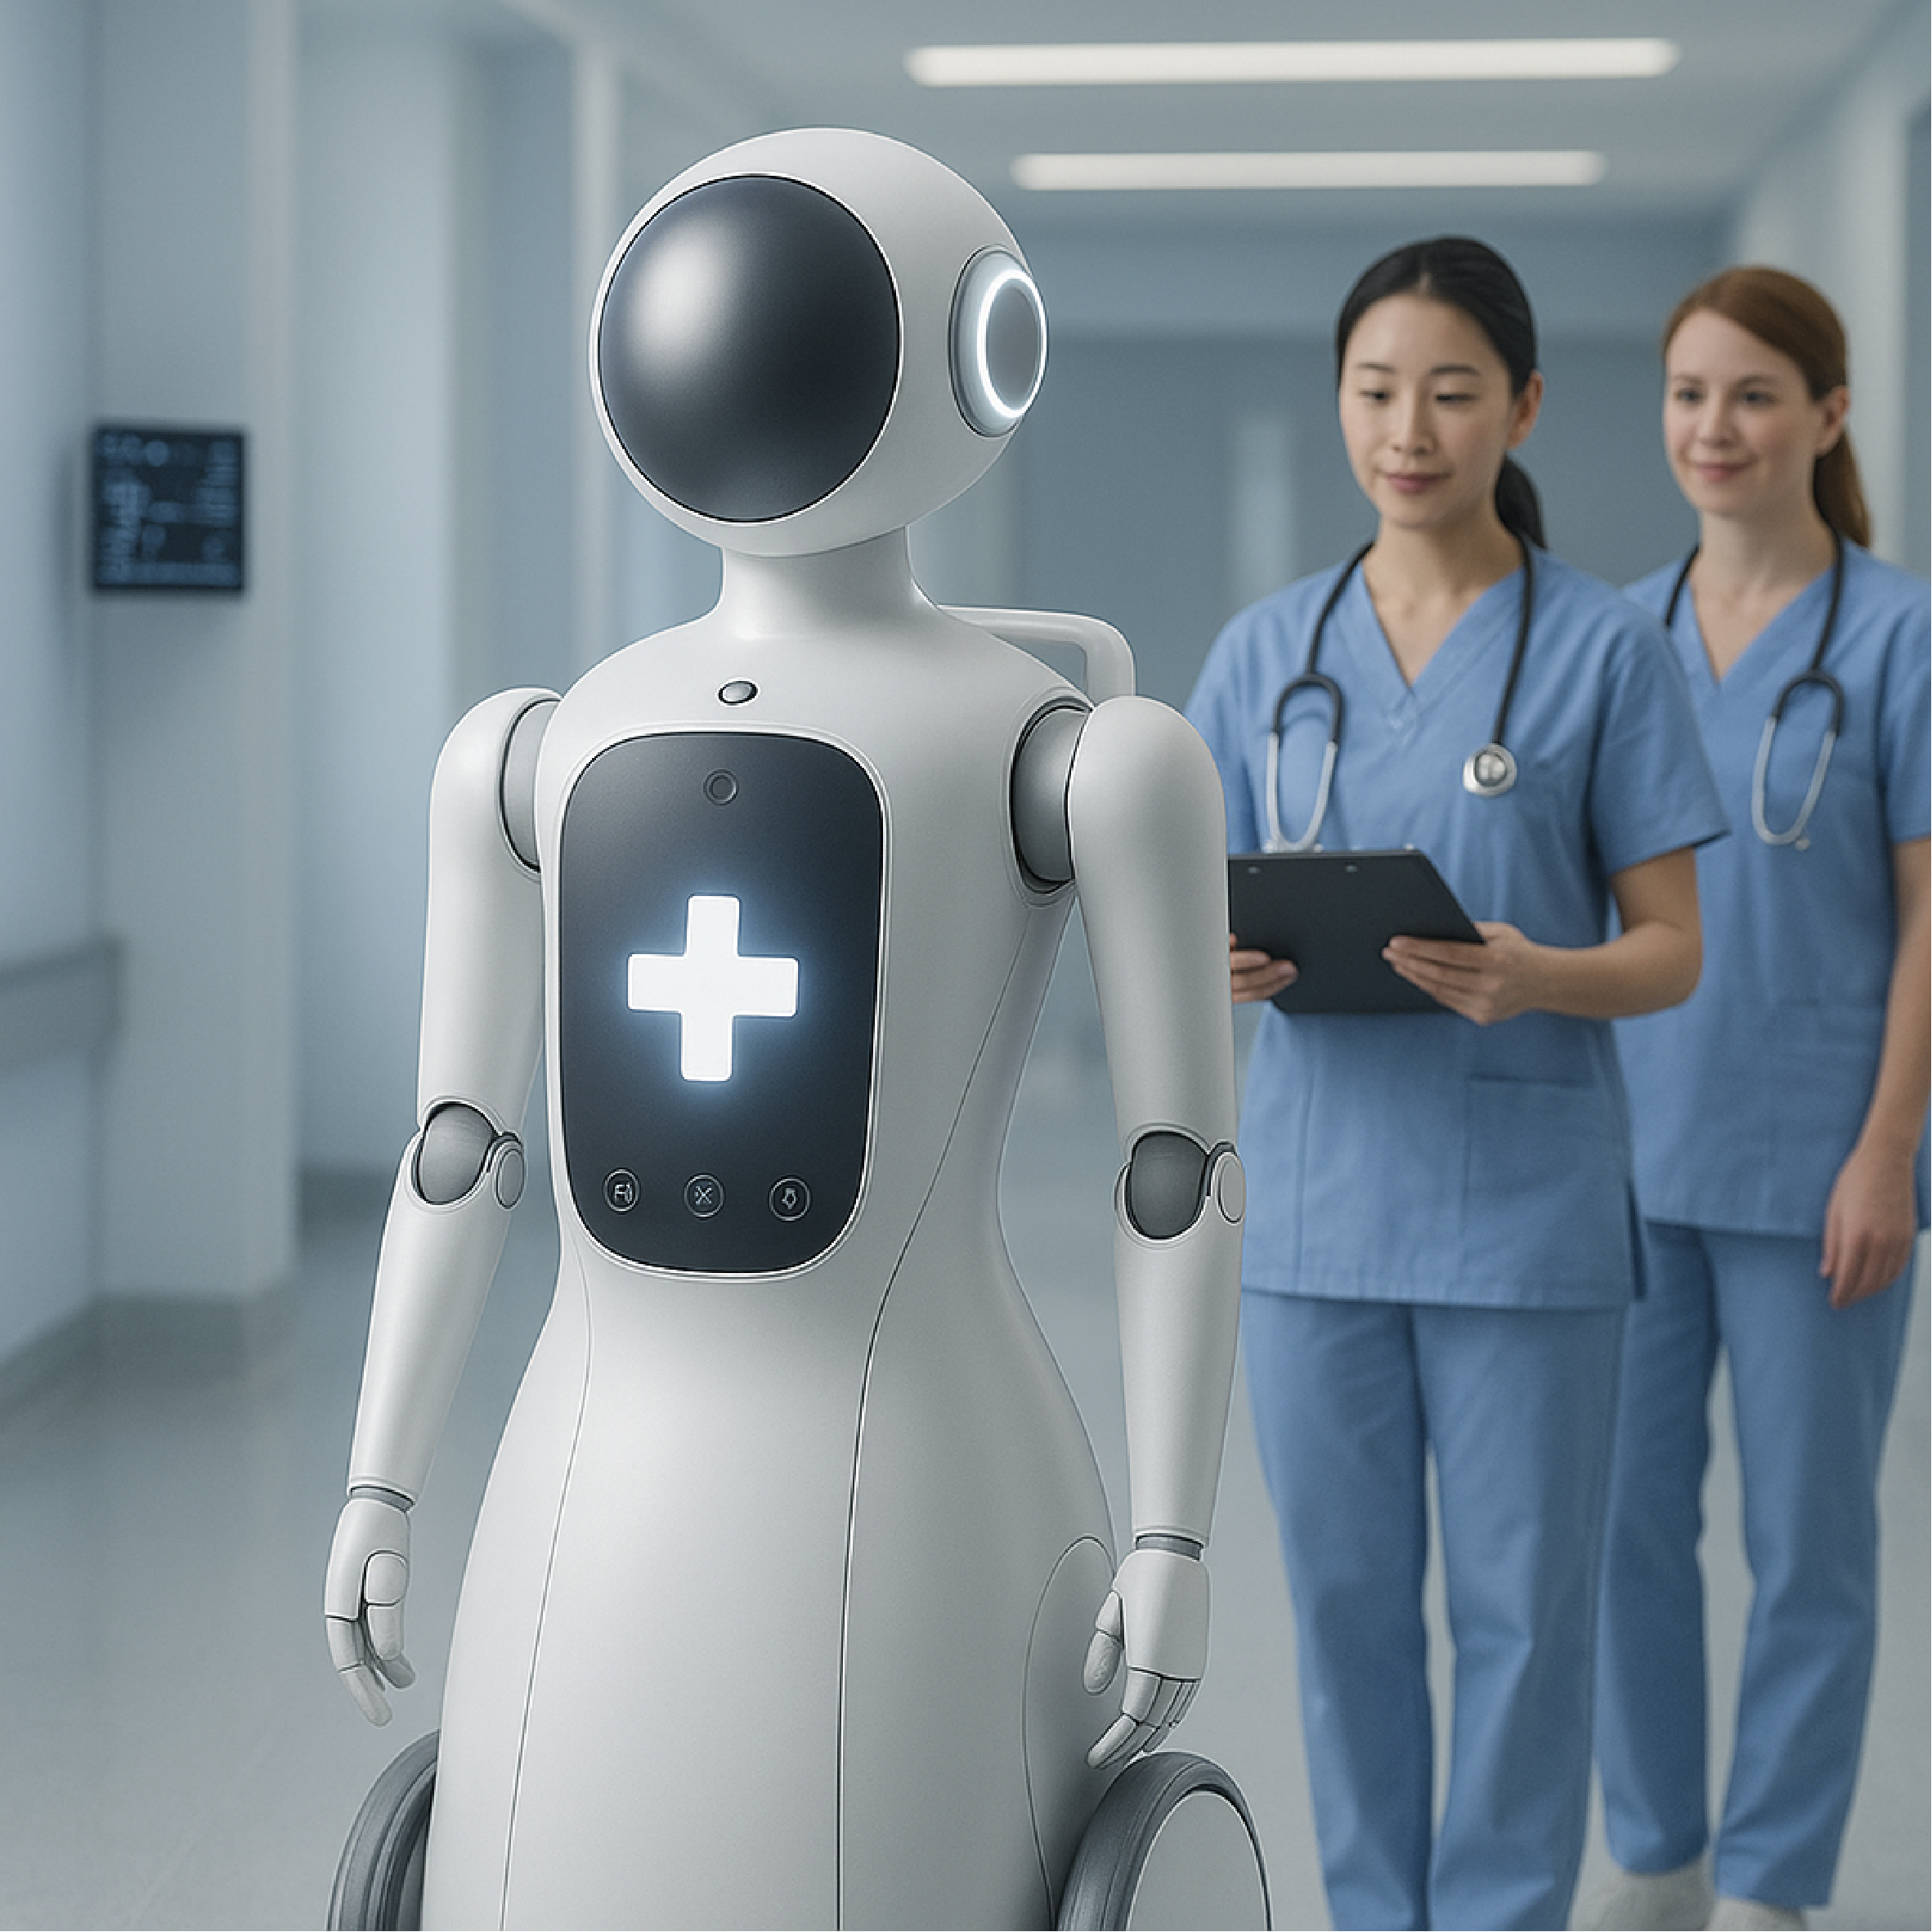

AI로봇

AI로봇

간호 서비스AI로봇이 의료 현장에서 간호사를

도와 간호 업무를 수행하고 업무의

효율성을 높여드립니다. -